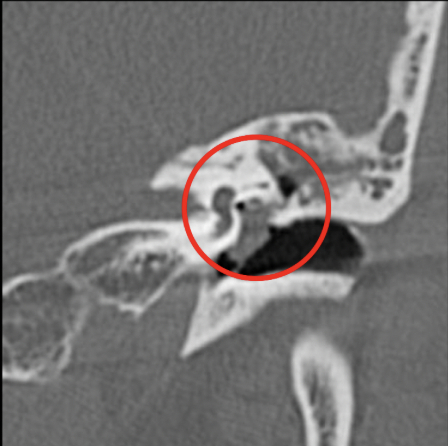

Cuál es tu diagnóstico?

A

Otitis media

Mejor estudio de imagen y clave diagnóstica de otitis media

• TC

• Masa bien definida en oído medio (densidad intermedia) + erosiones osiculares